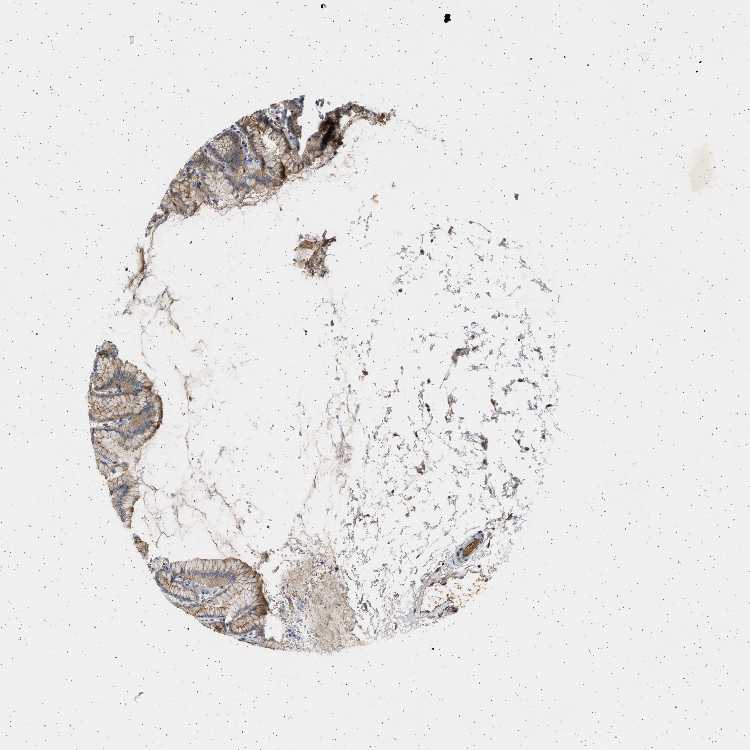

STOMACH 1 - Antibody stainingi

Antibody staining in the annotated cell types in the current human tissue is reported as not detected, low, medium, or high, based on conventional immunohistochemistry profiling in selected tissues. This score is based on the combination of the staining intensity and fraction of stained cells.

Each image is clickable and will lead to virtual microscopy that enables deeper exploration of all samples and also displays staining intensity scores, fraction scores and subcellular localization as well as patient and tissue information for each sample.

Antibody HPA018096

Glandular cells Medium